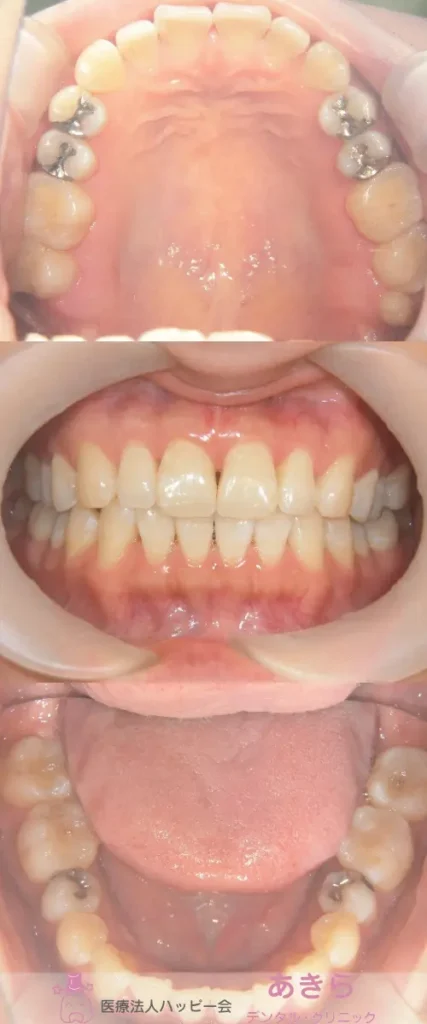

SH療法

SH療法-症例-No.012-外傷歯を伴う叢生(凸凹)の矯正症例

山形市の歯医者「あきらデンタル・クリニック」のSH療法の症例をご紹介します。 SH… -